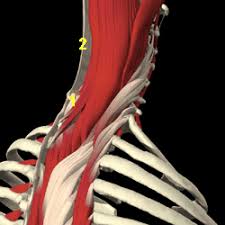

Ligamentum Nuchae : Trapezius Occipital Ligamentum Nuchae Clavicle Acromion Muscle Anatomy Art Movement Scapula : It extends from the external occipital protuberance and median.

Ligamentum Nuchae : Trapezius Occipital Ligamentum Nuchae Clavicle Acromion Muscle Anatomy Art Movement Scapula : It extends from the external occipital protuberance and median.. Nuchal ligament creates the median fibrous septum in the middle of the muscles of the two parts of posterior neck. Medical definition of ligamentum nuchae: ( plural ligamenta nuchae ). The ligamentum flavum forms a cover over the dura mater: Looking for online definition of ligamentum nuchae in the medical dictionary?

The ligamentum nuchae are very strong. Ligamentum nuchae — das nackenband (ligamentum nuchae) ist ein paariges band aus elastischem bindegewebe, das als rückenseitige verspannung der halswirbelsäule dient. A median ligament of the back of the neck that is rudimentary in man but highly developed and. The ligamentum flavum forms a cover over the dura mater: The ligamentum nuchae is a ligament that forms a strong, fibrous median partition between the muscles of the two sides of the back of the neck.